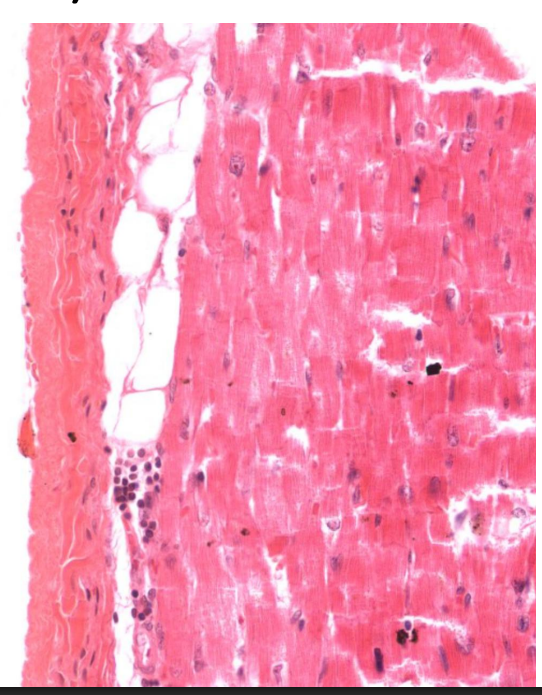

What structure is this?

Myocardium of the left ventricle

What is special about the myocardium?

Cardiac muscle

Thickest layer

Ventricle folds = trabecular carnae